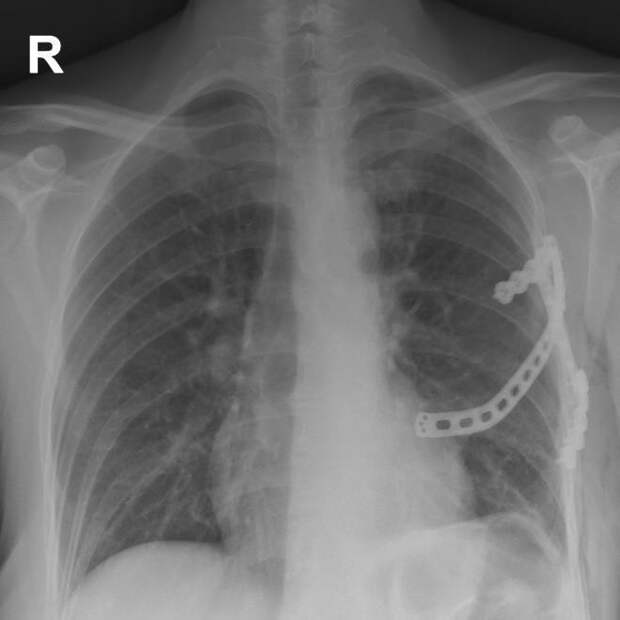

Для решения проблемы на основании данных КТ с помощью 3D-печати был разработан индивидуальный трехреберный титановый протез. Для минимизации повреждения мягких тканей и костных структур дополнительно был создан пластиковый макет для «примерки» будущего изделия.

В ходе операции междисциплинарная команда в составе торакального хирурга Алексея Паршина и травматолога-ортопеда Ярослава Рукина установила имплант размером 12 см через разрез всего 5 см.

«Для лучшего заживления надкостница с ребер была частично удалена, выполнена туннелизация в грудной мышце. Макет импланта был установлен в подготовленное ложе и намечены точки фиксации. После титановый протез был установлен и зафиксирован специальными винтами. Рану послойно ушили с применением безузлового внутрикожного косметического шва», — добавил Алексей Паршин.

Послеоперационный период протекал без осложнений. У пациентки сохранена полная подвижность руки и дыхательная функция. Сейчас она выписана домой в удовлетворительном состоянии.